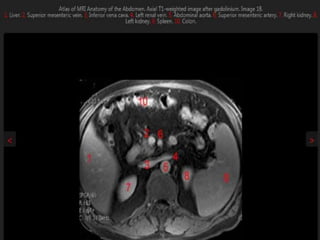

MRI anatomy images of the abdomen.

MRI -Magnetic ResonanceImaging. • Uses a high-field magnet to image the body. •Rapidly switching magnetic field gradients align the precession of the H protons (water and fat). •When the gradients are turned off, a faint radiofrequency signal is produced. • Image is reconstructed using Fourier transforms. • Multiplanar and vascular assessment possible.

MRI anatomy imagesof the abdomen.